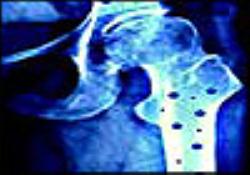

ترکیب پلاستیک و سلولهای بنیادین برای ترمیم مشکلات استخوانی

دانشمندان دانشگاه های ادینبورو و ساوتهامپتون با استفاده از ترکیب سلولهای بنیادین و یک ماده سخت تجزیه‌پذیر، موفق شدند شرایطی برای رشد دوباره استخوان واقعی فراهم آورند.

به گزارش خبرگزاری مهر، محققان ماده ای با یک ساختار لانه زنبوری تولید کرده اند که این امکان را دارد که جریان خون از میان آن عبور کند و شرایطی را برای سلولهای بنیادین مغز استخوان بیمار فراهم می آورد که به این ماده چسبیده و استخوان جدید رشد کند.

طی زمان این پلاستیک تجزیه می شود و استخوانی که به تازگی رشد کرده جایگزین این مواد پیوندی می شود.

براساس یک بیانیه، دانشمندان این مواد را با ترکیب سه نوع پلاستیک تولید کرده اند. آنها برای تولید این پلاستیک از تکنیک ترکیب استفاده کرده و صدها ترکیب پلاستیک را برای شناسایی ترکیبی که قوی و سبک باشد و همچنین بتواند از سلولهای بنیادین پشتیبانی کند، تهیه کردند.